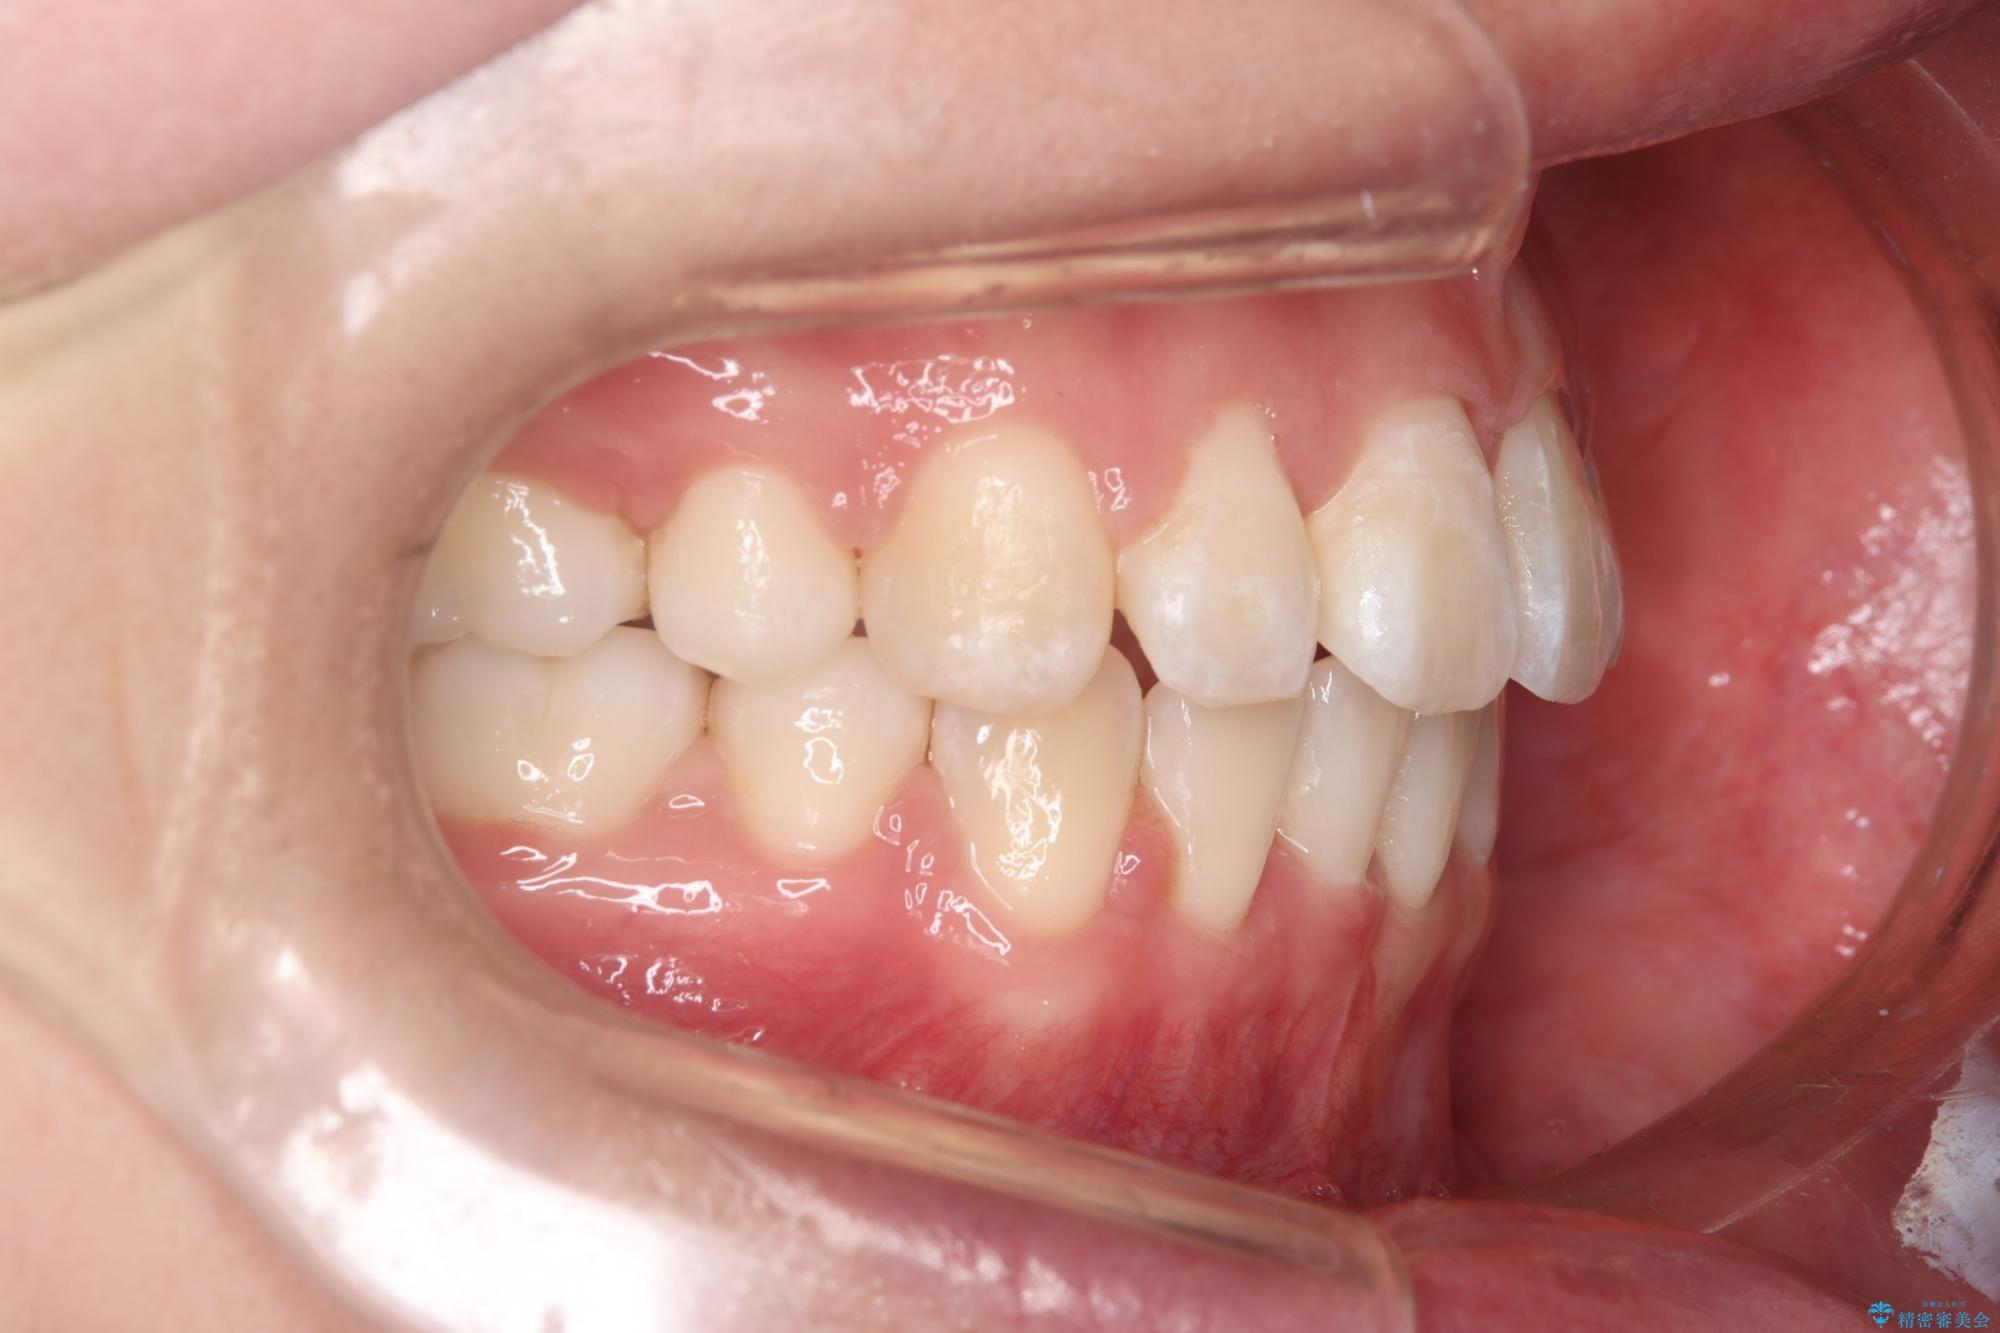

前歯のガつきと口元が出ていることを気にされご来院された患者様です。

上下4番目の歯を抜歯してガタつきを改善しながら口元を下げる治療計画を立てました。

抜歯矯正で口元を下げたことで、Eラインが大変綺麗になりました。